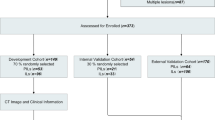

In this study, we retrospectively evaluated patients who underwent minimally invasive pneumonectomy with a clear pathology of pulmonary nodules at the Qilu Hospital of Shandong University between January 2020 and January 2022. The inclusion criteria were as follows: (1) patients with a single intrapulmonary nodule based on a chest CT scan performed within 1 month before surgery; (2) patients with lung nodules with maximum diameter ≤ 2 cm; (3) patients with pGGN without any solid component as indicated via CT imaging; (4) absence of pulmonary atelectasis and active inflammation based on lung images; (5) clear pathological findings obtained after surgical resection; (6) asymptomatic at diagnosis; and (7) no preoperative treatment. The exclusion criteria were as follows: (1) aged < 18 years, (2) history of thoracic surgery, (3) incomplete perioperative data, (4) history of malignant disease within the past 5 years, and (5) metastatic tumors. The patients included in our study were screened according to the inclusion and exclusion criteria (Fig. 1). Further, we used a random split-sample approach to randomly assign all the enrolled patients to either the training cohort or validation cohort at a ratio of 7:3. The training cohort was used to develop the prediction nomogram, while the validation cohort was used to verify the performance of the nomogram.

The procedure for identifying and selecting eligible patients is illustrated in Fig. 1.

A total of 563 eligible patients were included in this study. Among these patients, there were 48 cases of benign nodules and AAH, 163 were AIS, 178 cases of MIA, and 174 cases of IAC. Further, we classified all the cases under the non-IACs (n = 389) or IACs (n = 174) groups, according to the criterion, “whether the nodule had IAC characteristics.” We then randomly assigned the enrolled patients to either the training cohort (n = 395) or validation cohort (n = 168) in a 7:3 ratio; no significant differences existed between the two cohorts with respect to any of the variable (Table 1). Thus, there were 273 non-IAC and 122 IAC cases in the training cohort and 116 non-IAC and 52 IAC cases in the validation cohort. The characteristics of the training and validation cohorts are presented in Table 2.